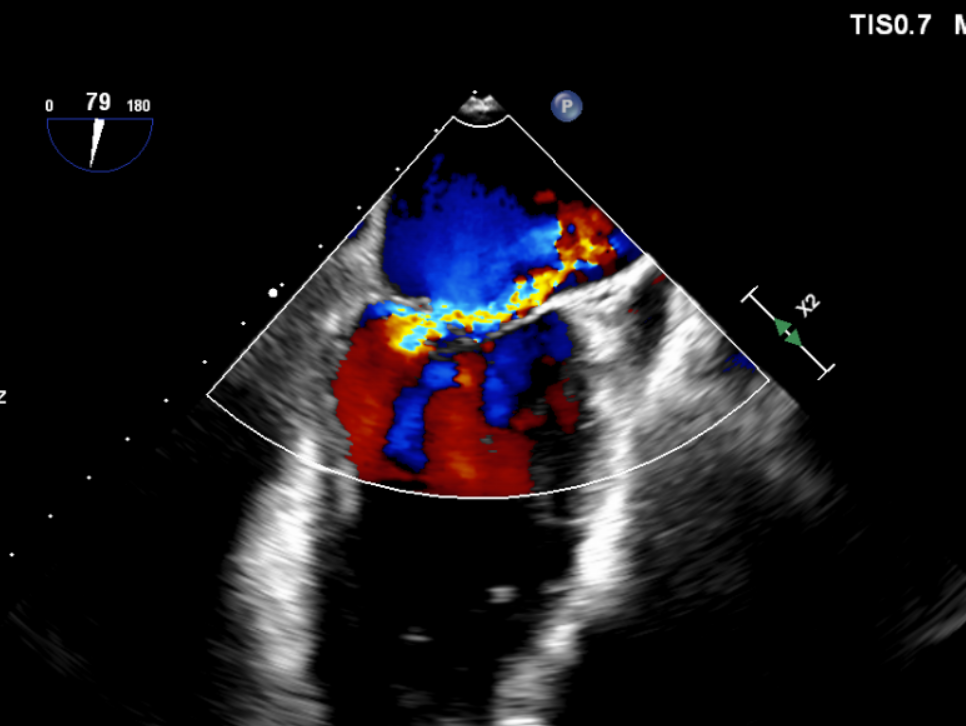

基线显示二尖瓣大量反流

复查超声,P3区无反流,仅2区微量中心性反流